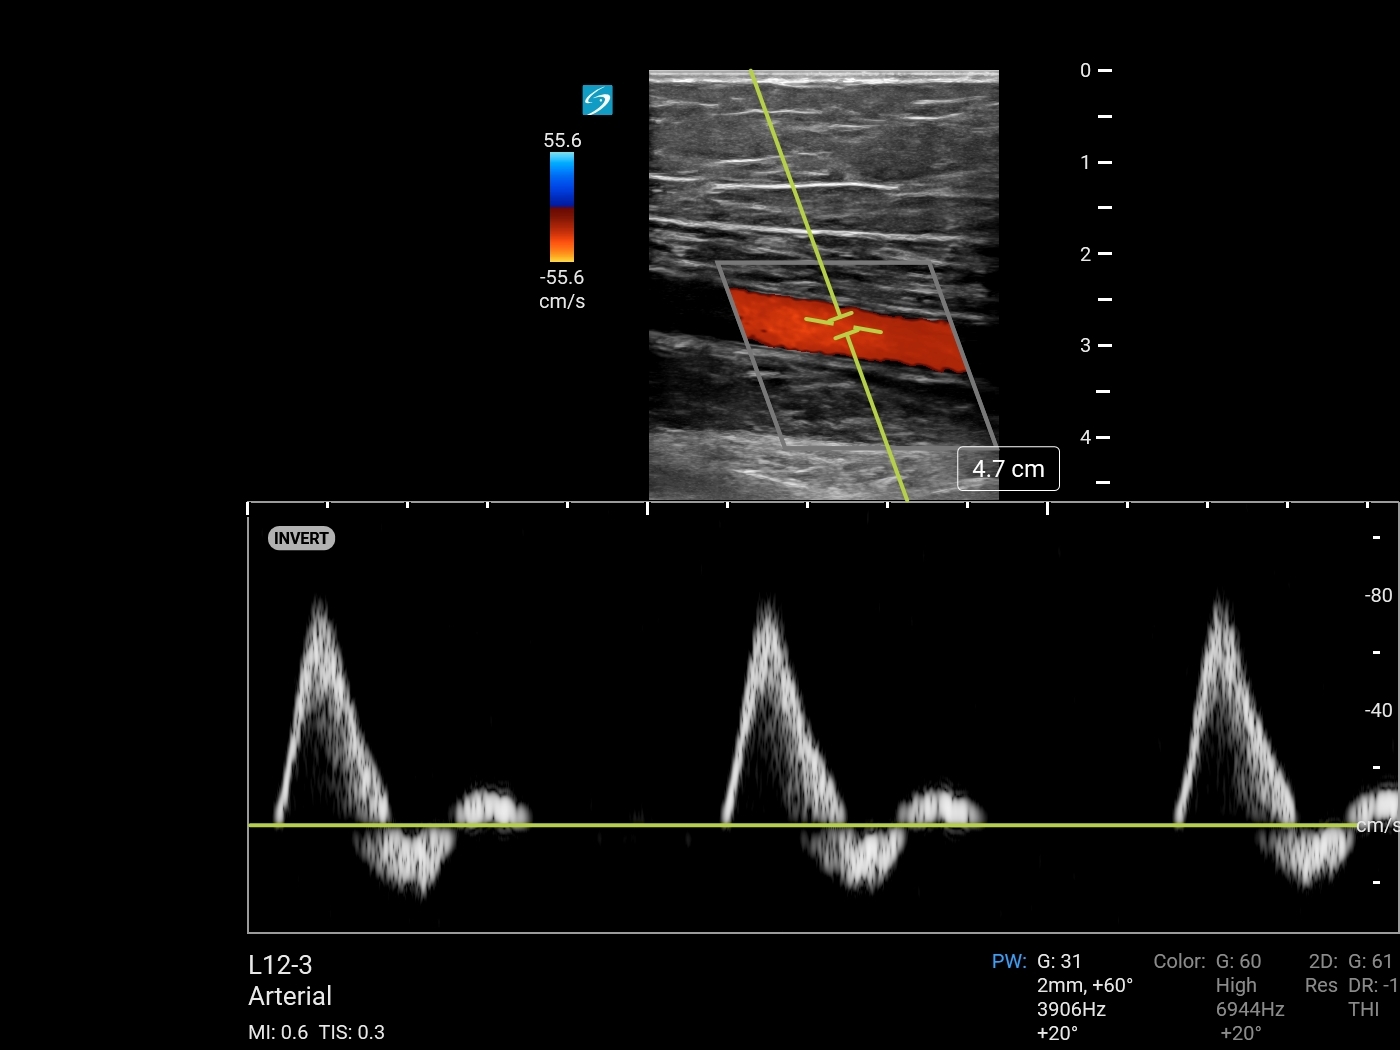

Color Power Doppler (Sonosite PX L12-3) Image